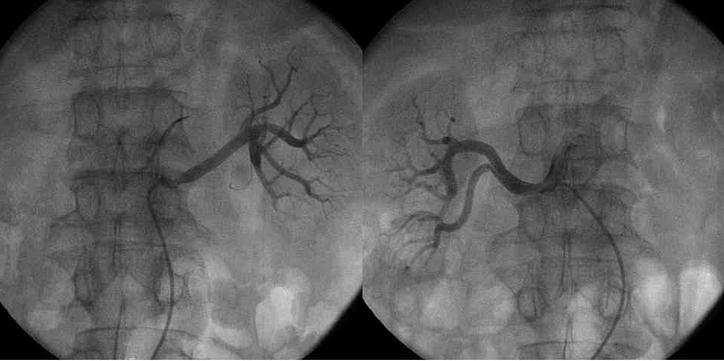

一侧肾脏的血管造影图

两侧肾脏的血管造影图